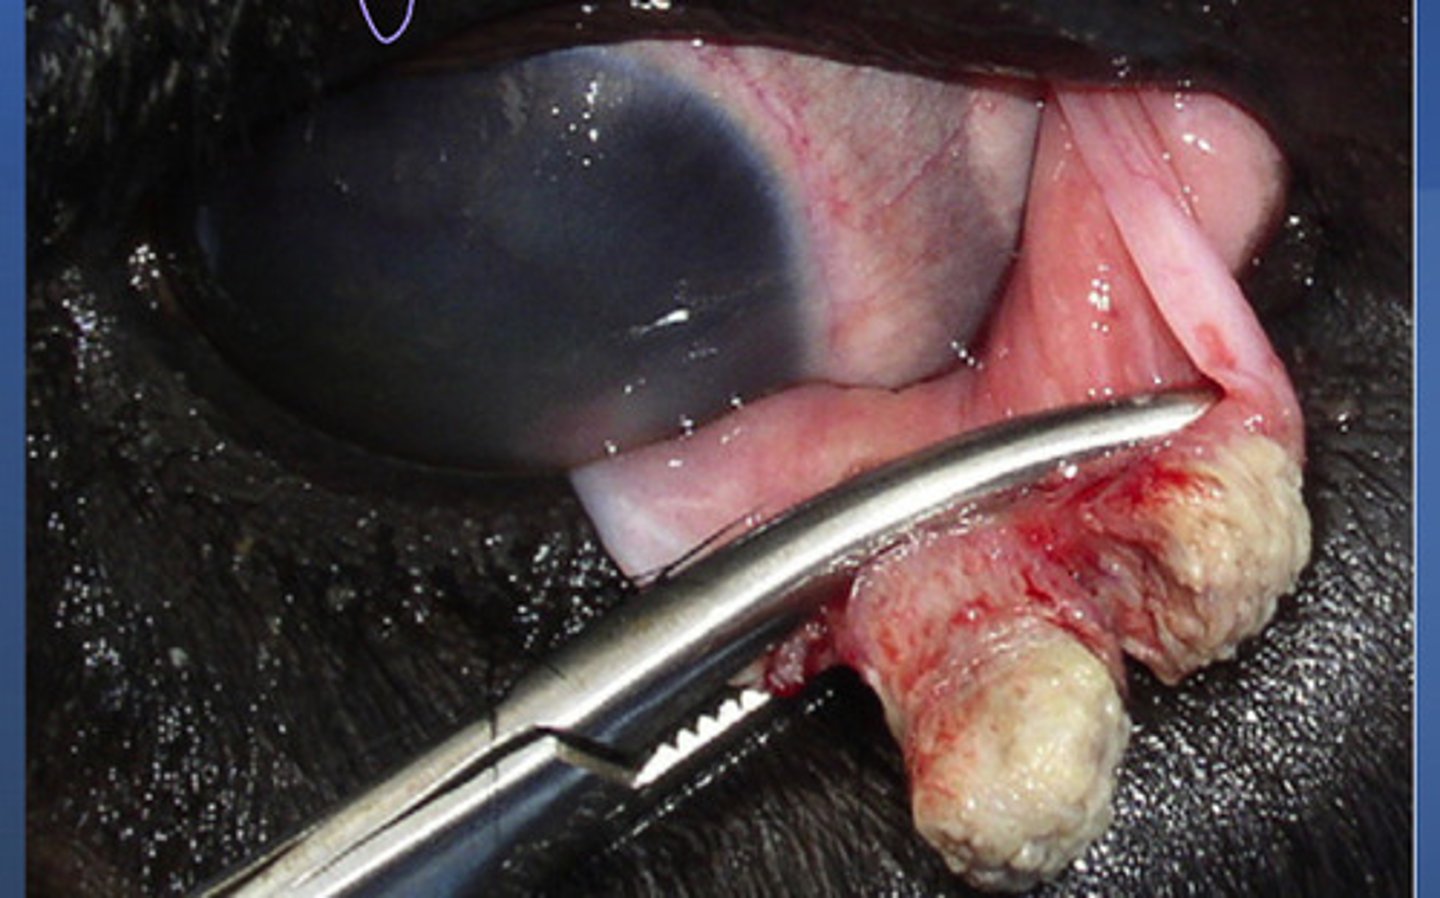

Warts = bovine papillomavirus

What is happening in this cow?